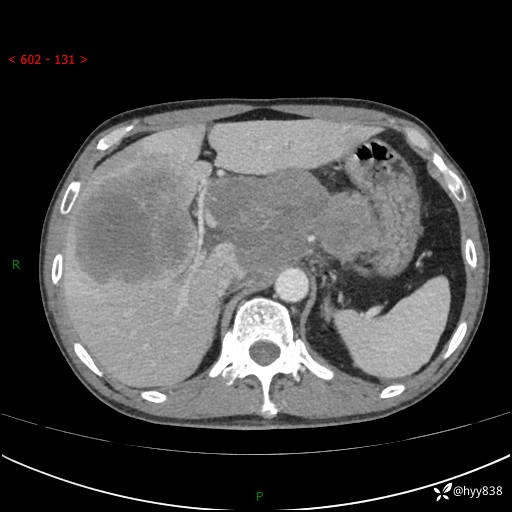

上腹部CT平扫+增强(两期)